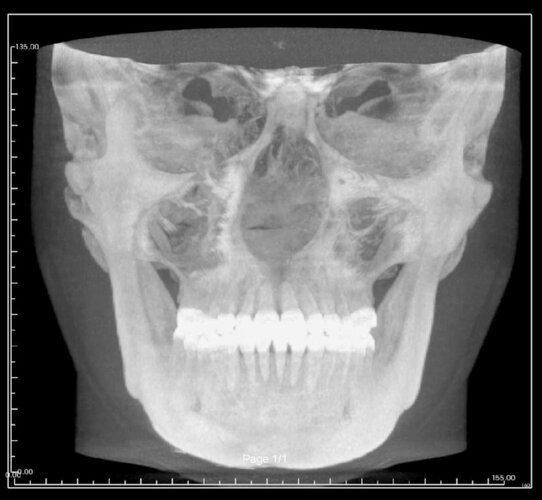

Needing serious advice on what would best surgeries for myself. I’m currently exploring double jaw surgery and rhinoplasty for my subhuman face.

My maxillofacial surgeon has suggested a segmental upper jaw, lower jaw and genioplasty; will cost 12k but I have to wait a year for insurance to cover the hospital side which is 30k… I’m not interested in going overseas for this either.